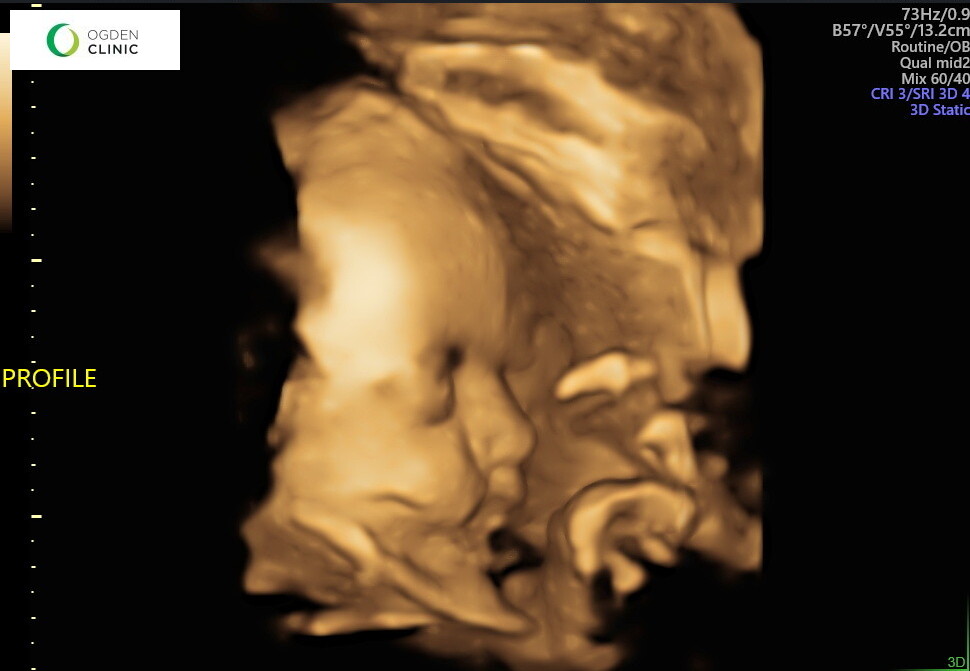

Baby bro is looking so cute! We loved getting some ultrasounds of him this month and seeing his cute face up close. He’s a mover, always has his hands covering his face in ultrasounds, and we are so excited he’s coming so soon!